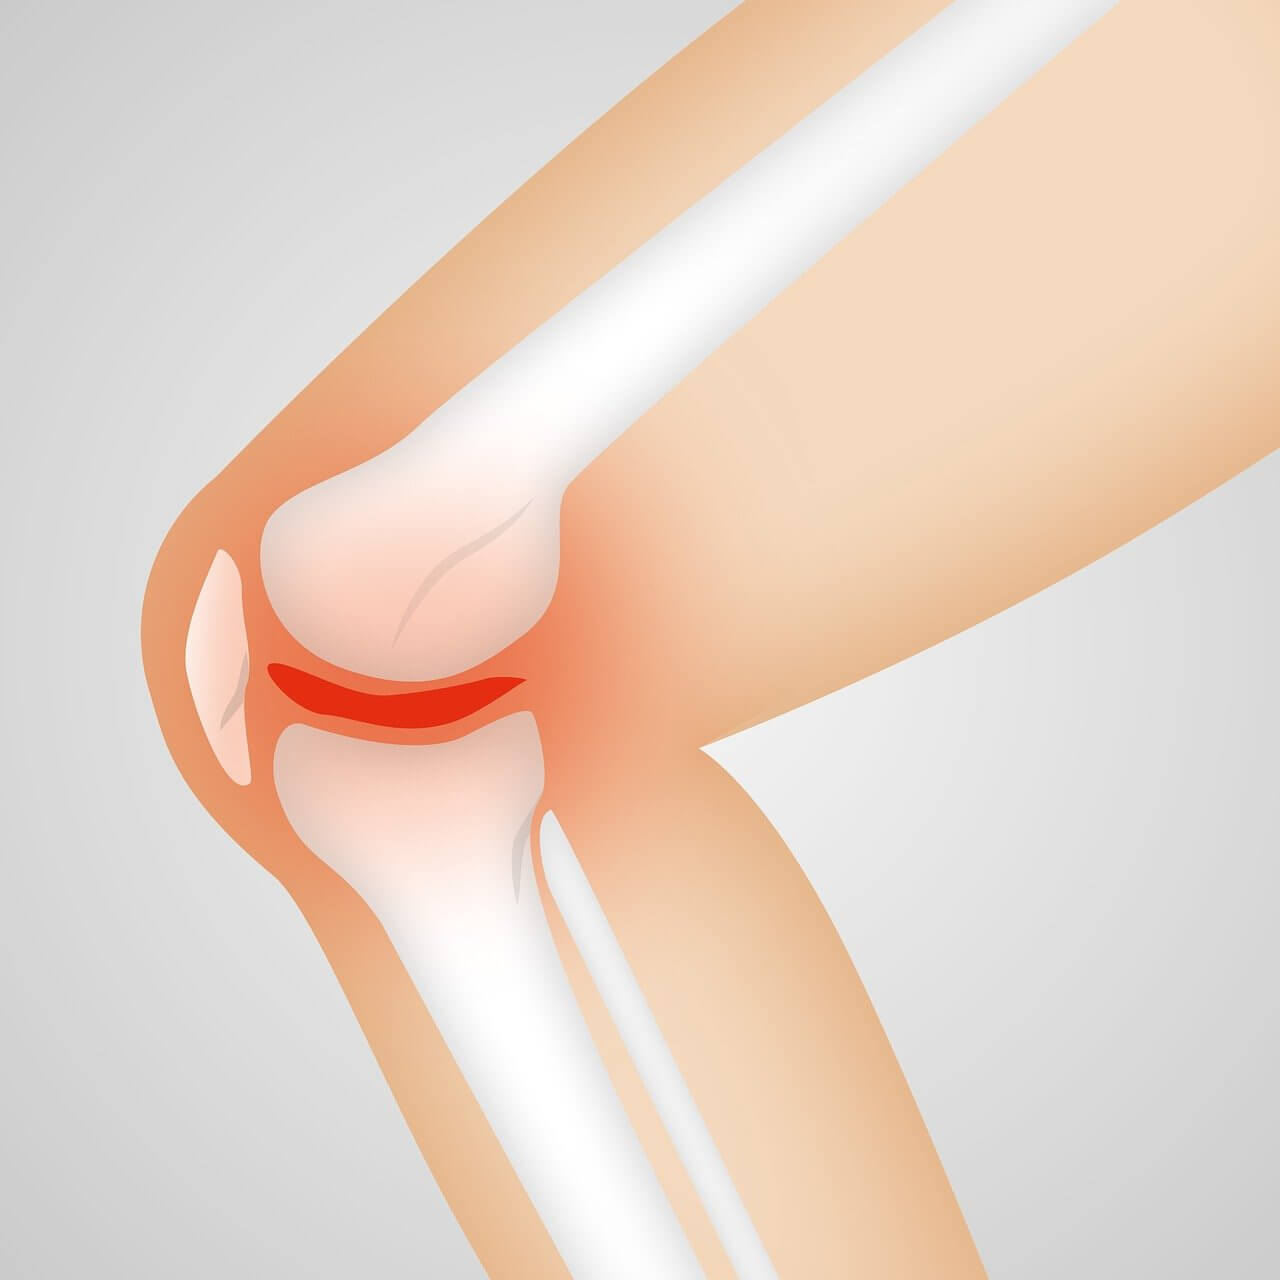

전방십자인대는 무릎 안쪽 깊숙이 위치하며 대퇴골과 경골을 연결해 무릎이 앞뒤로 흔들리지 않도록 잡아주는 역할을 합니다. 쉽게 말해, 무릎의 중심을 지탱하는 ‘핵심 줄’과도 같습니다. 전방십자인대 파열이 일어나면 무릎이 헐거워지고, 체중을 지탱하기 어려워집니다.